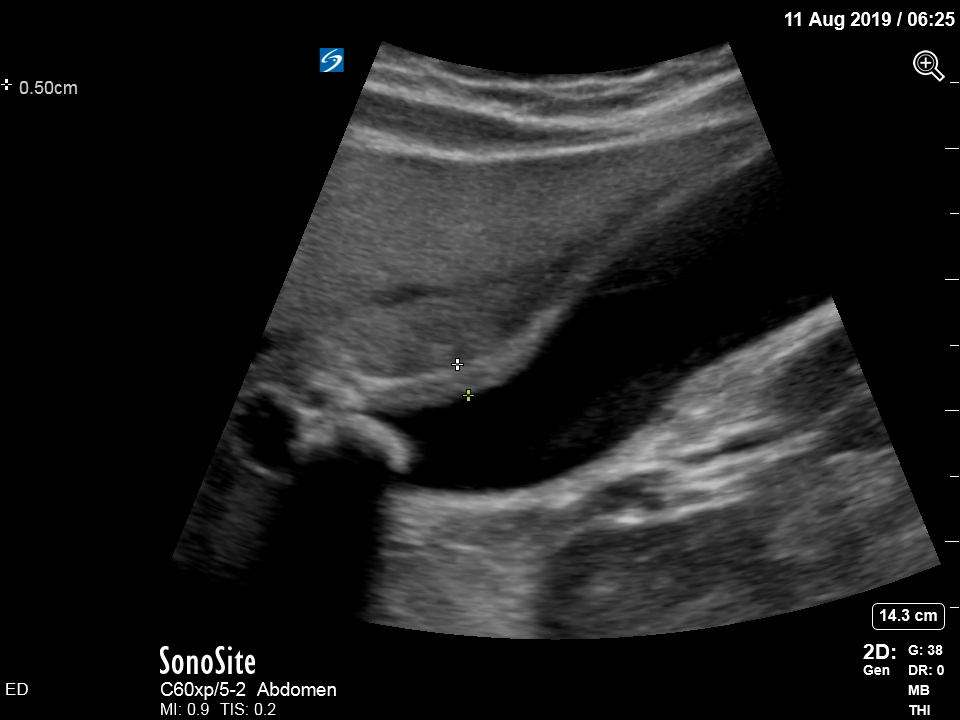

The treating house officer suspected an alternative pathology and bedside ultrasound was performed.

The appearance is typical of acute cholecystitis. The patient was started on IV antibiotics. Images were shown to the surgical registrar who accepted the patient for admission. Formal ultrasound confirmed the findings and the patient went for laparoscopic cholecystectomy within 24hrs. At operation, there was a grossly inflamed gallbladder with an 11mm stone in the neck.

Ultrasound is the formal imaging study of choice for diagnosing gallstones and acute cholecystitis, which makes it a particularly useful POCUS study. The four sonographic signs of acute cholecystitis are:

- Cholelithiasis (stones in the gallbladder, especially if non-mobile)

- Gallbadder wall thickening (there are various published criteria and rules of thumb but generally >4mm is considered abnormal – though it is more about the edematous/irregular appearance than the specific number)

- Pericholecystic fluid

- Sonographic Murphy sign (the patient is tender when the probe presses on the gallbladder)

Notice the typical appearance of the gallstone – the anterior face reflects ultrasound producing a hyperechoic (bright) surface. Because no sounds waves pass through the stone, the area behind it cannot be imaged and instead we see the artefact known as posterior acoustic shadow.